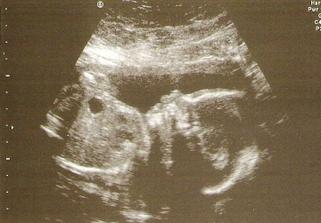

● KO 6.4. UTZ + poradna vše dopadlo dobře máme zdravé miminko které zodpovídá začátku 15tt 😀